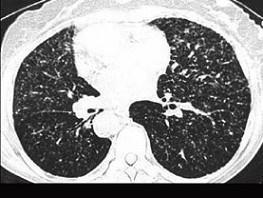

问题 女,23岁,消瘦盗汗1月余,干咳1周,偶痰中带血,影像如图,最可能的诊断为 ( )

选项 A、慢性支气管炎 B、SLE肺部侵犯 C、含铁血黄素沉着 D、弥漫性肺纤维化 E、粟粒性肺结核

答案 E